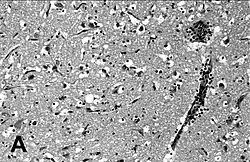

La maladie de Carré des phoques parfois aussi appelée peste des phoques est une maladie proche de la maladie de Carré du chien mais affectant principalement les phoques et autres pinnipèdes. Elle est causée par un morbillivirus appelé Morbillivirus phocae (anciennement Phocine distemper virus ou PDV). La maladie créa plusieurs épidémies notables dans les pays nordiques, en 1988 entraînant la mort de 23 000 phoques communs et en 2002 avec plus de 30 000 morts. Certaines études montrent que ce virus est aussi responsable de la mort soudaine d'un grand nombre de loutres de mer sur la côte pacifique de l'Alaska.